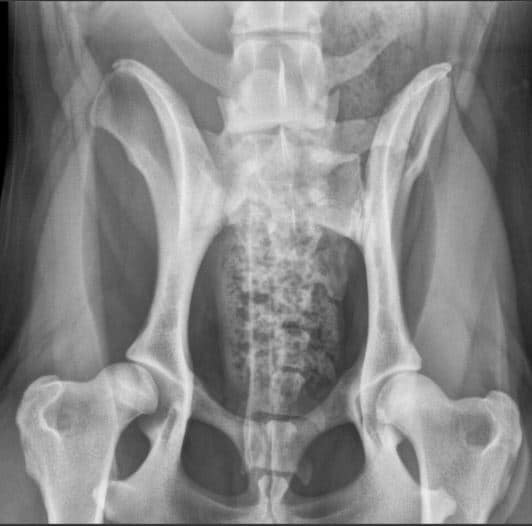

A normal canine spine consists of 7 cervical (C1-7), 13 thoracic (T1-13), 7 lumbar (L1-7) and 3 sacral vertebras (S1-3) resulting the total of 30 vertebras. Calculation starts from first thoracic vertebra (T1). The number of caudal vertebras (CD) vary.

Sacrum connects the lumbar spine to pelvis. It’s a part of the pelvis and it lies between the lumbar spine and tail. Sacrum is strong, triangular in shape and it sits between the hip bones. Normal sacrum consists of three fused vertebral segments; S1, S2 and S3.

LTV0